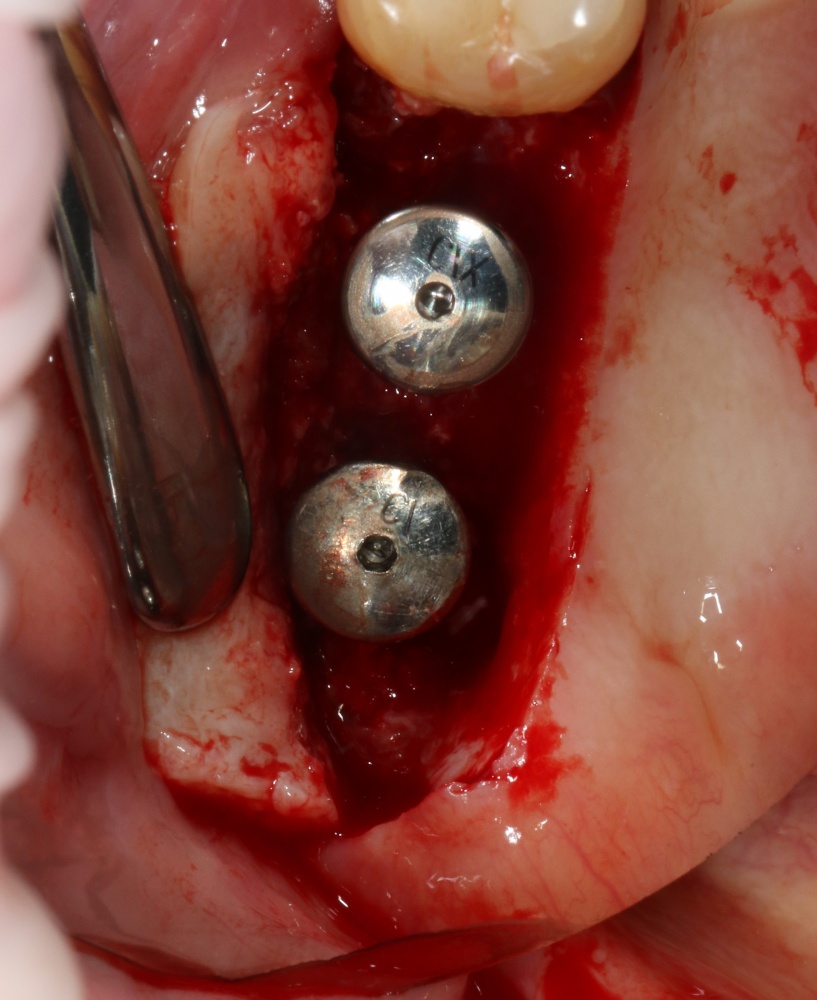

Вернемся к нашему клиническому случаю. Мы уже поставили импланты с расчетом на будущую высоту альвеолярного гребня и положение будущих зубов:

И, если в предыдущей части мы рассматривали ситуацию, когда принимающее ложе имеет относительно простой рельеф, и у нас не возникло сложностей с адаптацией аутоблока, то в случае, рассматриваемом сегодня, нормальная и точная адаптация крупного костного фрагмента, практически, невозможна. Именно поэтому мы решили использовать направленную костную регенерацию (НКР), поскольку с адаптацией тестообразного по консистенции графта проблем, обычно, никогда не бывает. Как, например, в этом случае:

С помощью него мы «достраиваем» недостающую часть альвеолярного гребня, полностью перекрывая импланты. Напомню, что субкрестальные Ankylos Dentsply Implants вполне допускают такой подход.